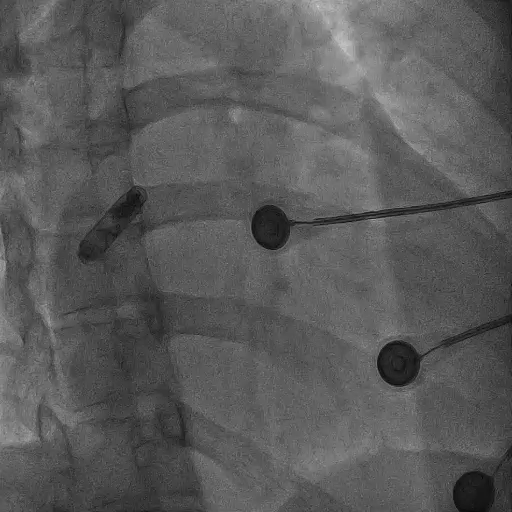

整个植入过程十分高效顺利,耗时30分钟,术中测试下腔阻抗280Ω,从mapping至对接栓模式阻抗高低变化:310Ω-320Ω-330Ω-320Ω-310Ω,张力测试确认头端螺旋固定牢靠;释放时阻抗来到340Ω,阻抗变化结合术中损伤电流参数显示植入位置心肌活性良好,释放后阈值测试1.75v*0.4ms,手术完美结束。术后第二天随访阻抗400Ω,P波感知1.3mv,阈值0.5v*0.4ms,各项指标均展现出理想状态,印证了本台手术的完美结果。

术后第二天参数